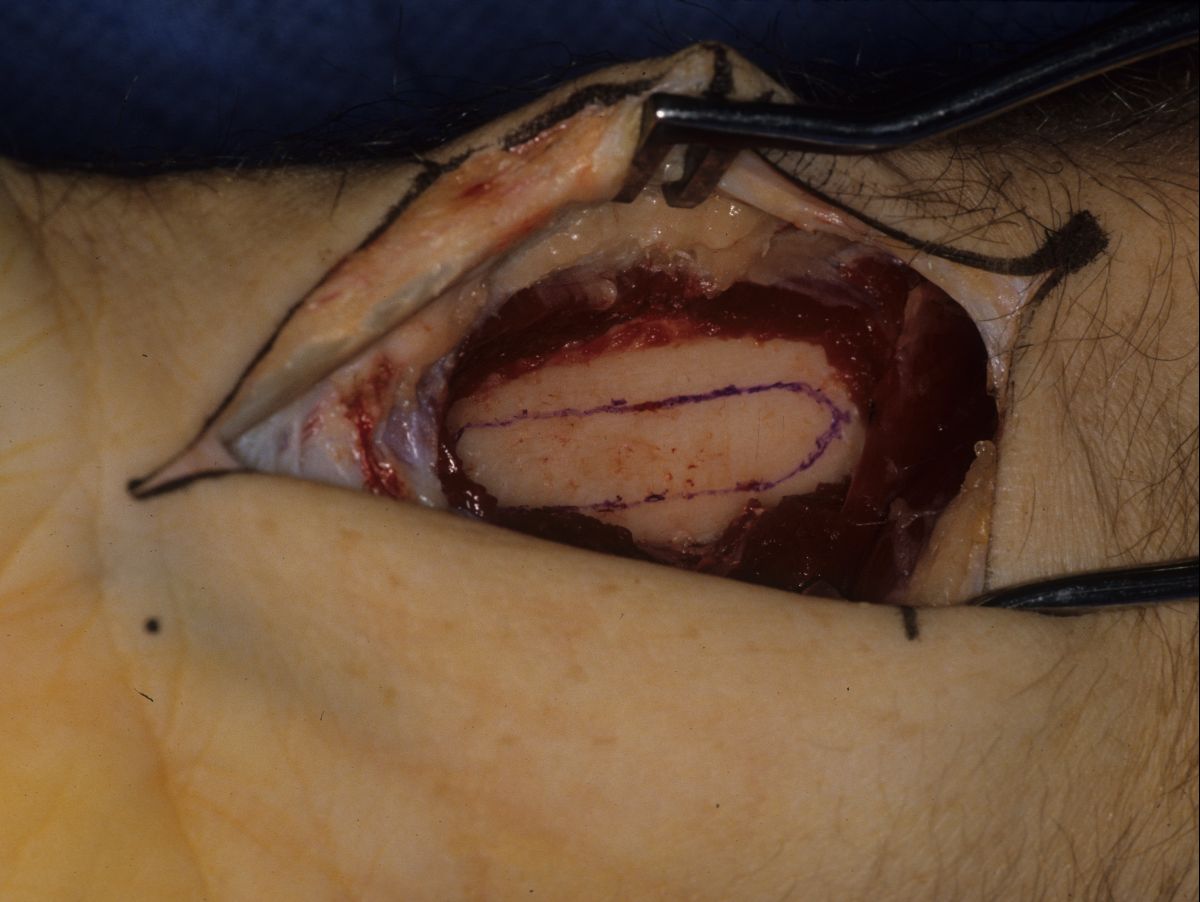

| This was approached through a midlateral incision extended around the tip to allow direct access to the nail bed. |

| A typical whitish smooth epidermal inclusion cyst was found protruding from the tuft of the distal phalanx. |

| The cyst was excised, and the cavity was debrided with a high speed burr. |